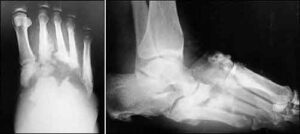

“Live Case Transmission” tra Abano Terme e Orlando – Florida: intervento di rivascolarizzazione estrema del piede diabetico trasmesso in diretta satellitare